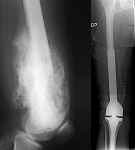

• Tumor surgery of the musculoskeletal system

• Resection of benign and malignant tumors of the bone and soft tissue

• Reconstruction of bone defects by biological procedures (from spongiosaplasty to bone transfer)

• Tumor total endoprosthesis (TEP) of all large joints and bones